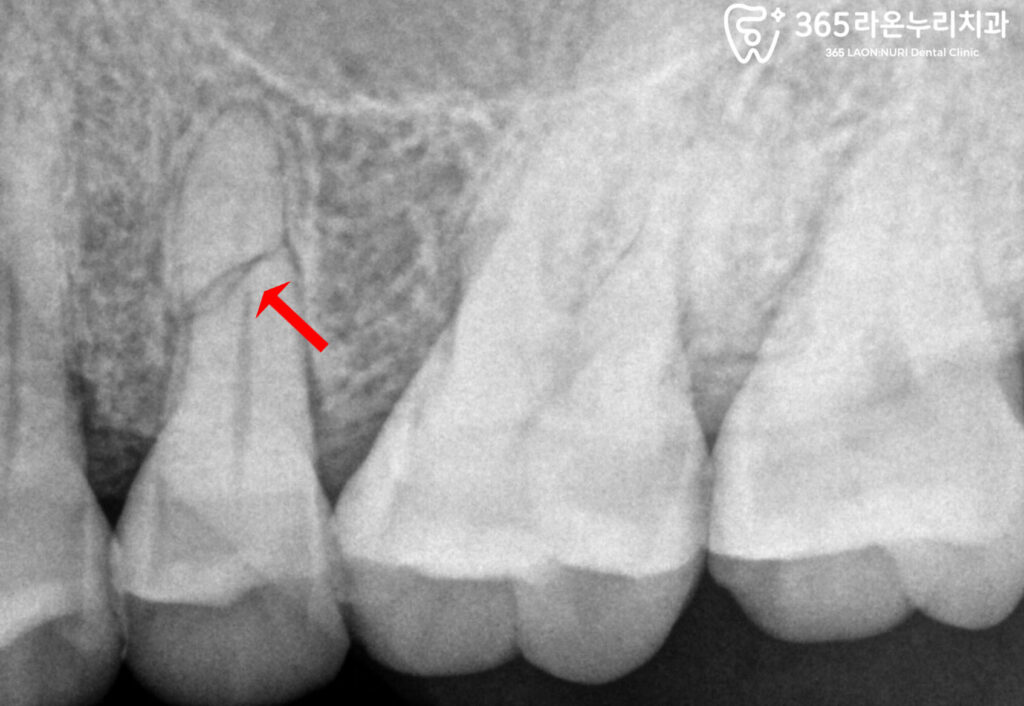

교익 + 치근단 촬영으로 확인한 수평 파절

25번 치근 중간 부위에

뚜렷한 가로선의 파절선이 관찰됩니다.

파절된 위치와 정도에 따라

살릴 수도 있고 발치해야 될 수도 있습니다.

보존 가능성이 낮아

장기적 예후가 불량할 때는

발치를 선택하는 경우가 많습니다.

이에 따라 오늘 케이스도

발치 후 임플란트 식립을 선택했습니다.